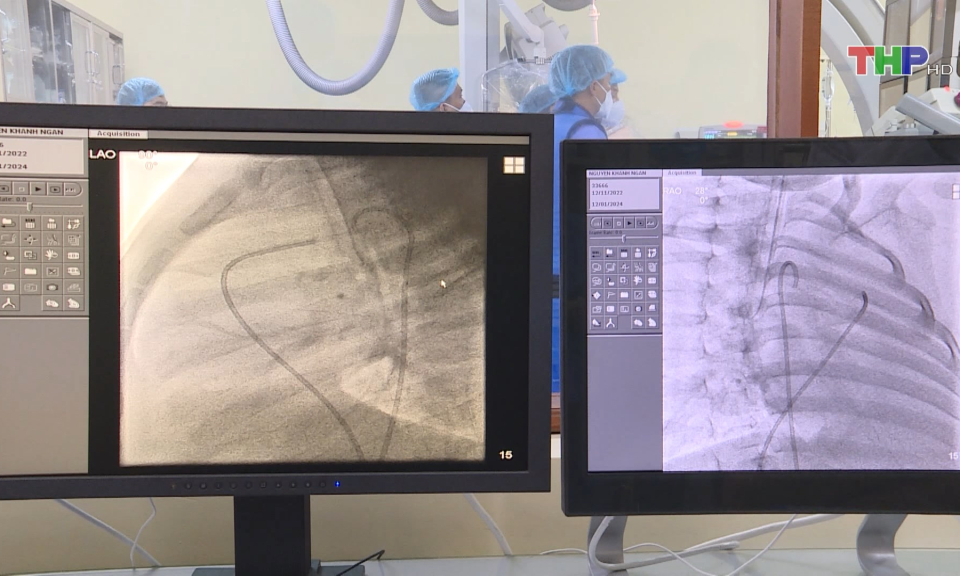

Can thiệp đóng ống động mạch thành công cho 3 bệnh nhi Bệnh viện Trẻ em Hải Phòng đã phối hợp với các chuyên gia Bệnh viện Nhi Trung ương thực hiện thành công 3 ca can thiệp bít ống động mạch bằng dù trên máy chụp mạch xóa nền cho 3 trẻ bị mắc bệnh lý tim bẩm sinh còn ống động mạch. 09:41 | 16/01/2024